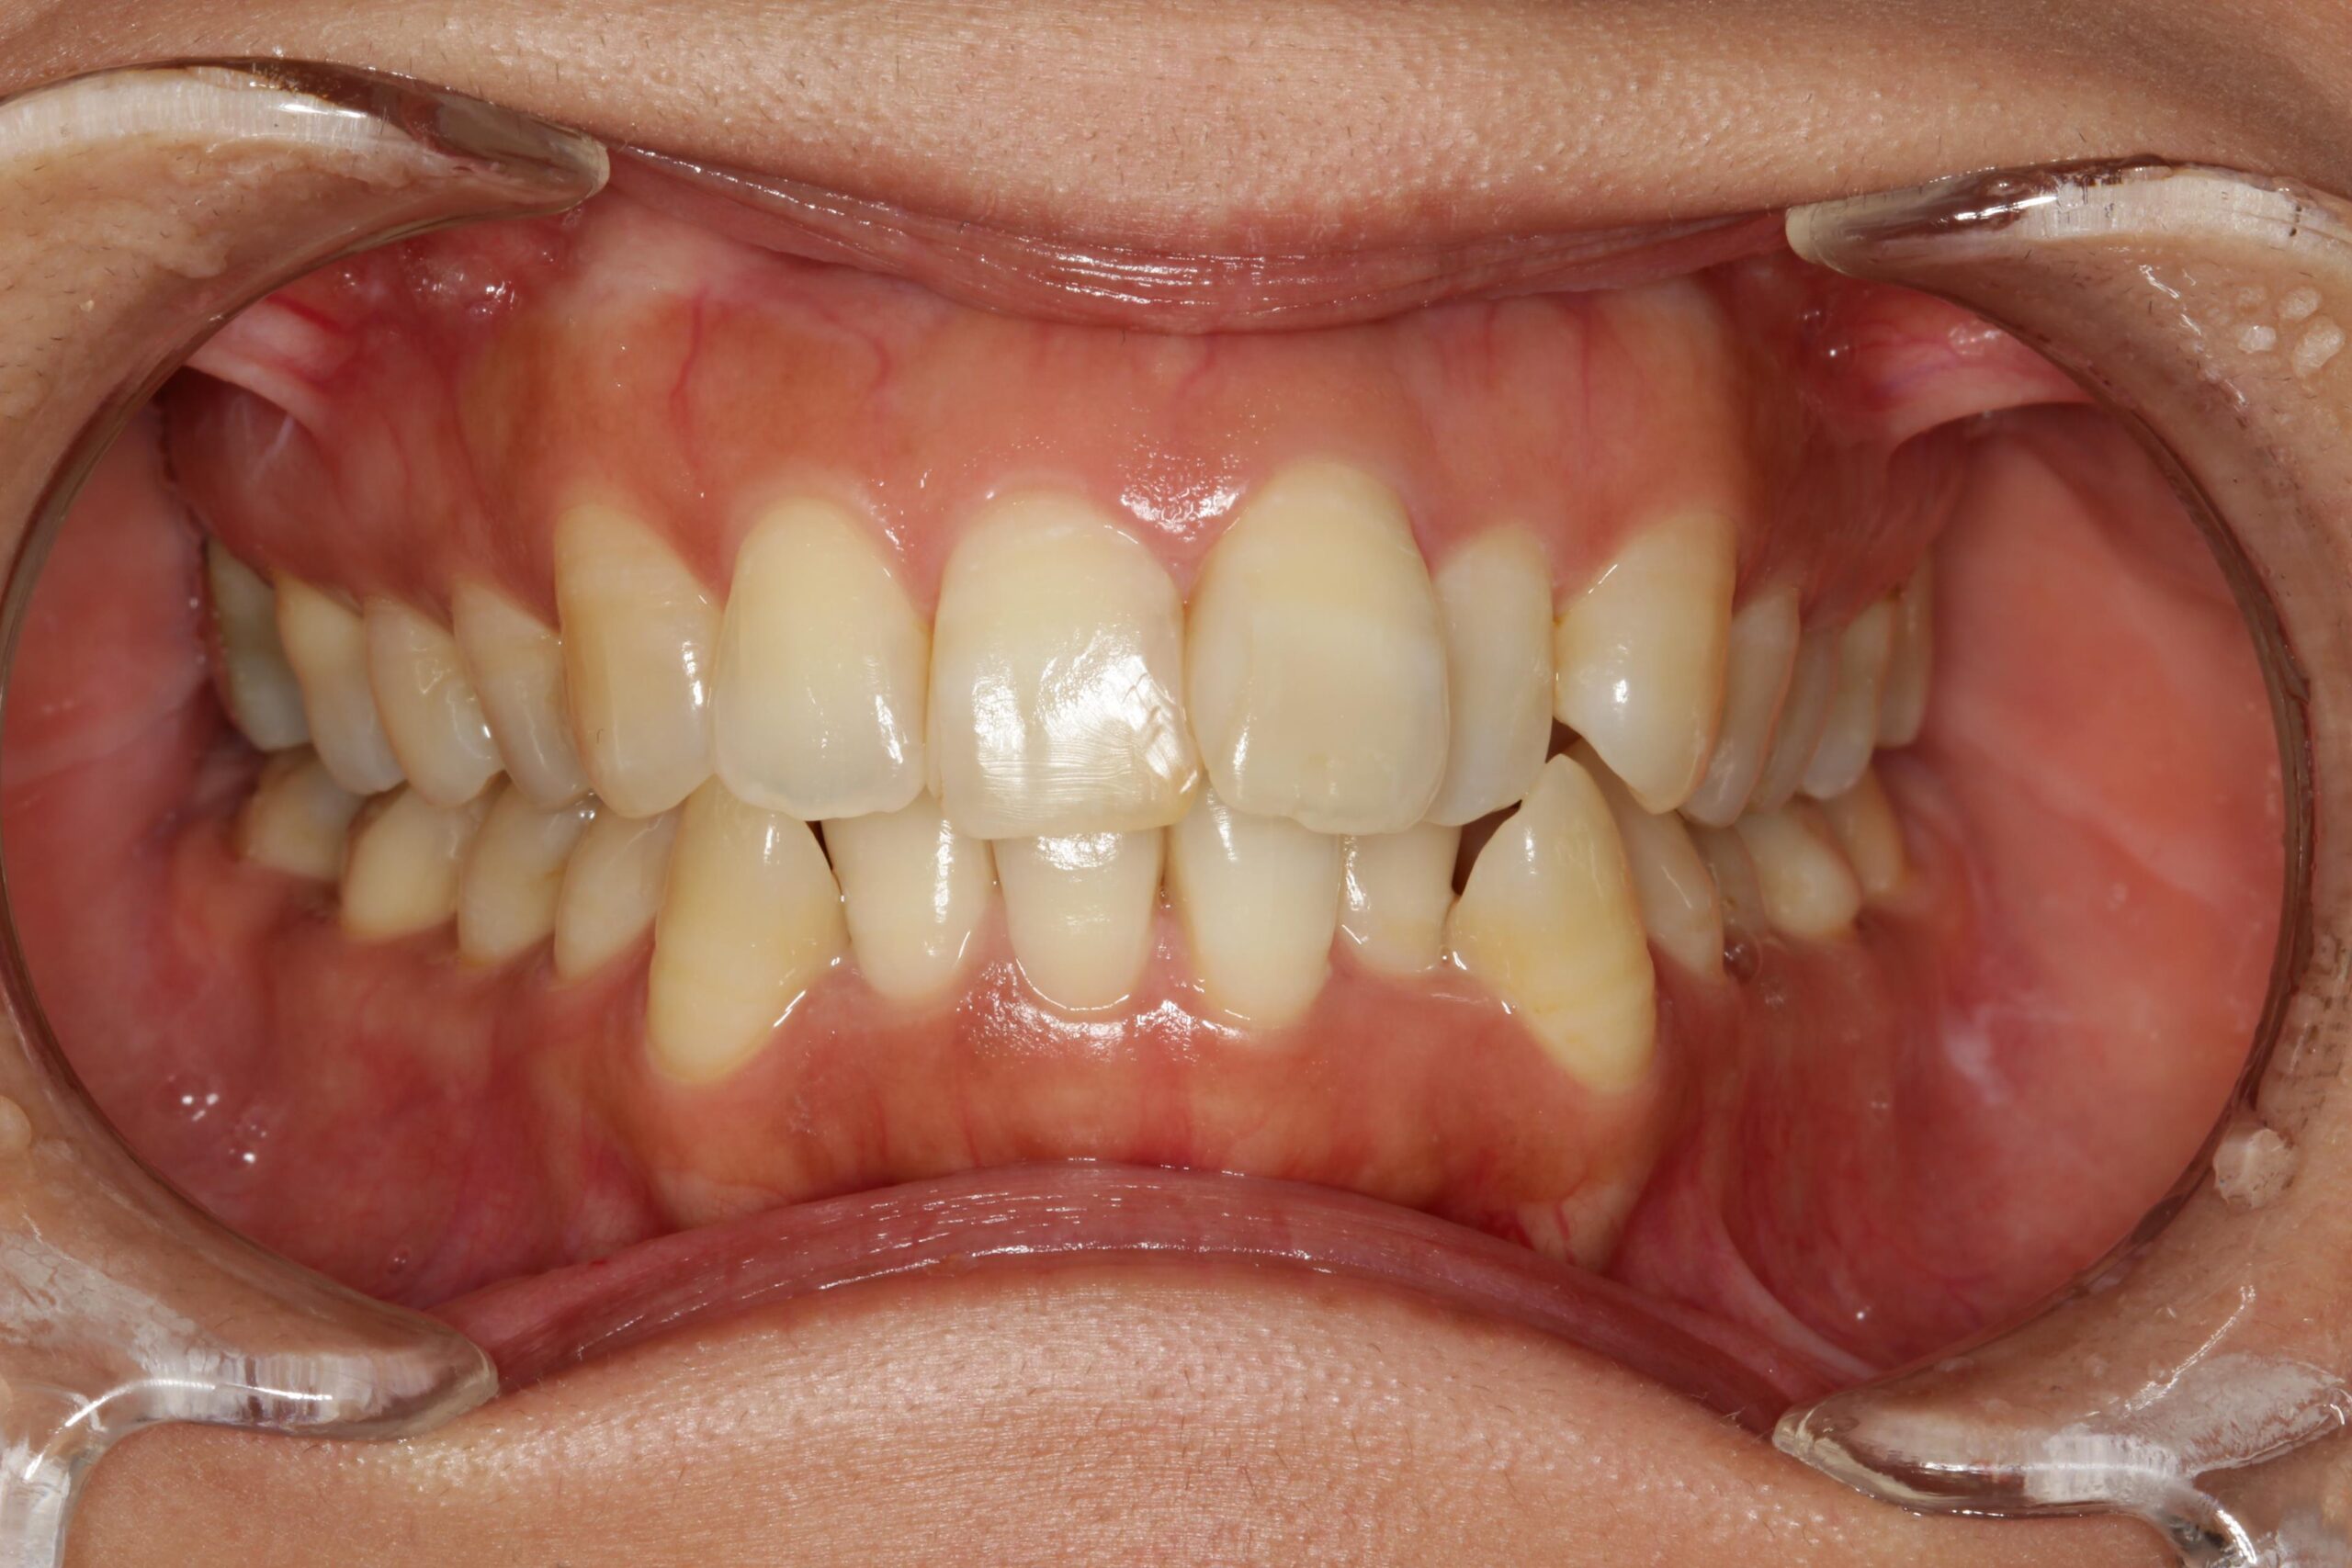

下の歯が上の歯よりも前に出ている状態です。

顎関節への負担や全身のバランスが悪くなる場合があり、お子様の場合は咀嚼が不十分になることで体の発育にも影響する可能性もあります。

よく噛むことは食べ物の消化のしやすさにも直結し、全身の健康にも影響します。

矯正治療で噛み合わせを整えることは、食事のしやすさの改善にも繋がります。